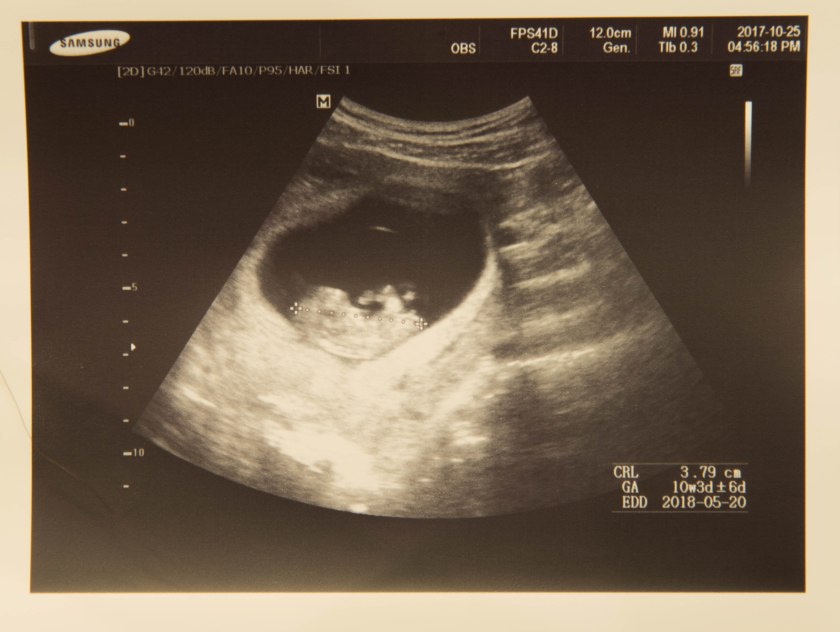

今天爸爸陪去妈妈洗完头之后,就去了妇产科门诊检查。因为上次没能陪妈妈去照超音波,这回能同妈妈一起来格外地兴奋,再上次爸爸看到小Puppy的时候还只是一个小咖啡豆大小。

就在做好了诊前检查,医生开始照超音波的时候,阿妈刚好跑了进来。因为医生和阿妈熟识,便让小Puppy和阿妈打个招呼,不知道是恰好还是视觉效果,银幕里小Puppy的手就真的在招手。阿妈非常兴奋地说道“我觉得真是老天帮忙。”,然后便和我么说刚刚出去找了很久都一直没有找到停车位,就在阿妈决定无论被不被罚款都停双黄线的时候有一个车位空出来了。就是那么巧,晚一分钟或许都看不到小Puppy招手,这真是谢谢老天道帮忙呀。

2017年的11月20日,从2017年8月12日开始算,妈妈怀孕刚好100天。从最初的受精卵细胞开始,宝贝你逐渐长大到现在已经比一个柠檬还大了。